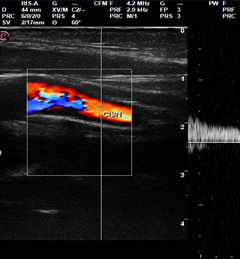

Per riconoscere precocemente e prevenire l’aterosclerosi occorre eseguire una visita medica in cui si valuti la presenza dei fattori di rischio cardiovascolari ivi compresa la misurazione della pressione arteriosa. Il primo esame da fare dopo la visita e la valutazione dell’assetto lipidico di cui sopra si à parlato, è l’esecuzione dell’EcoDoppler arterioso dei tronchi sovraortici. Mediante questo esame si possono visualizzare gli ispessimenti della parete arteriosa, che suggeriscono la presenza di placche aterosclerotiche, è possibile inoltre valutare la velocità del flusso sanguigno e la rigidità vascolare. Nel caso poi fossero presenti anche dei sintomi come un dolore al petto (angina) magari durante sforzo sarà indicata l’esecuzione di una angioTAC coronarica, tecnica in grado di rilevare la sede ed estensione di eventuali placche alle coronarie anche in assenza di sintomi. Altri esami cardiologici contemplano l’esecuzione ad esempio del test da sforzo che valuta la risposta del cuore e il suo funzionamento sotto sforzo, portando alla luce eventuali problemi cardiaci che potrebbero non essere evidenti a riposo.